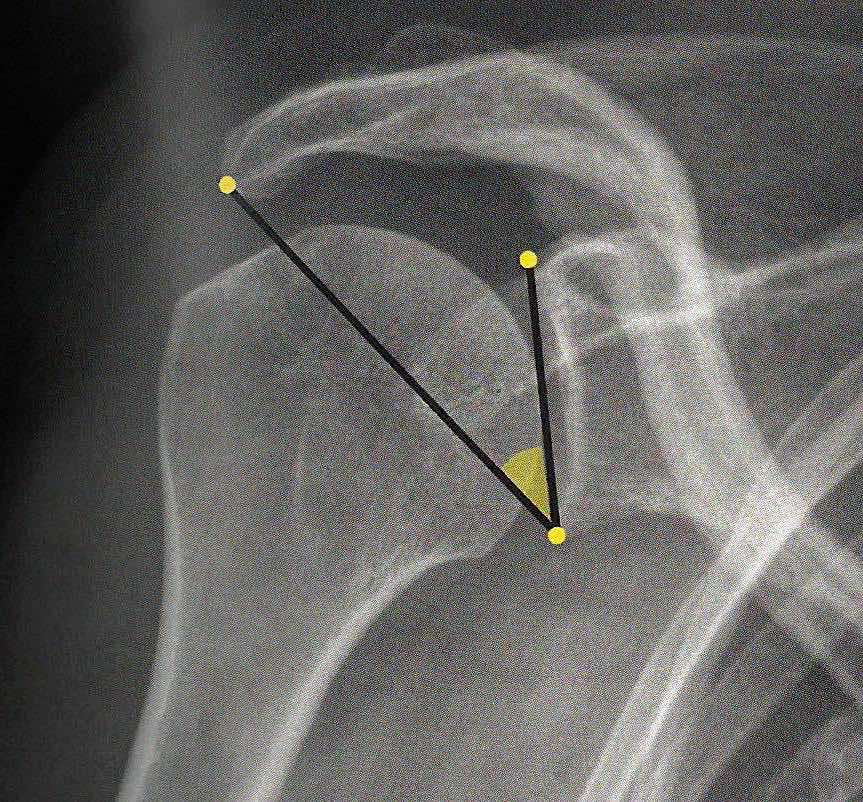

Pas de diminution de l'espace sous-acromial.

Respect de l'articulation acromio-claviculaire.

Intégrité de l'interligne articulaire gléno-huméral.

Pas de calcification en projection des tendons de la coiffe des rotateurs.

Pas de lésion suspecte dans les structures osseuses et les parties molles.

angle CSA < 30° arthrose / > 35° rupture coiffe

distance acromio-humérale < 7 mm rupture coiffe